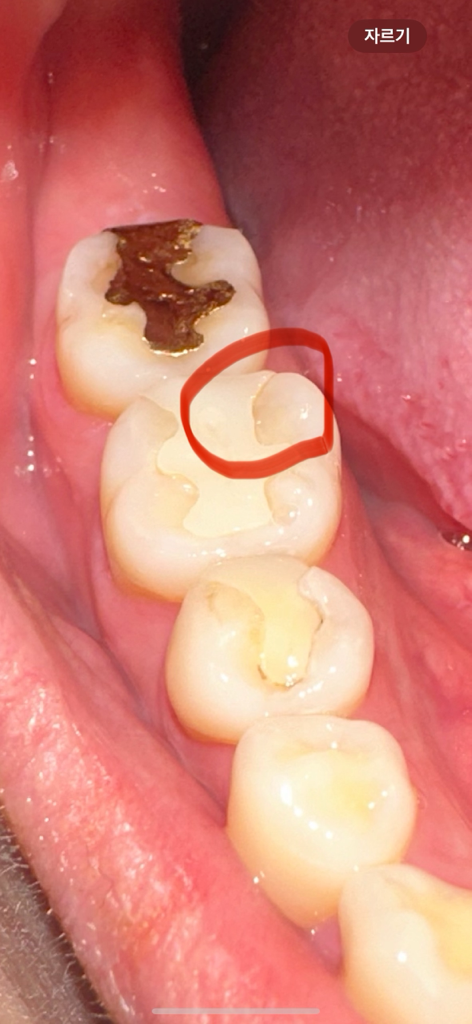

보철물이랑 치아 사이 틈이 생겼어요.. 눈으로만 봐도 충치인게 확실한걸까요? 한번씩 가끔 음식 씹을때 찌릿하곤 해요 ㅠㅠ 눈으로만 봐도 심각한가요?.. ㅜㅜ 무조건 보철물 교체를 해야하는거죠? 다음주 금요일에 치과 방문이 가능한데 그 기간동안 충치가 더 심해질까요? ㅠㅠ

• 2번 째 사진

부분적으로 치아를 수복하는 인내의 경우에는 시간이 지나면서 경계 부분이 착색이 되는 경우가 있습니다.

사진으로 봤을 경우에는 충치 보다는 착색이 가능성이 높아 보입니다.

또한 접착부위가 약해졌다면 사진처럼 보일 수 있습니다.

충치는 아닌거 같고 인레이가 시간이 지나면서 미세 틈이 생긴거 같으니 일단은 치과에 가셔서 체크를 받아보셔야될것같습니다 .

눈으로 보이는 것보다도 방사선 사진을 찍어봐야 할 것 같습니다. 일단, 현 증상과 함께 사진상 보이기로는 안쪽이 추가적으로 충치가 생겼을 확률이 있어보입니다.